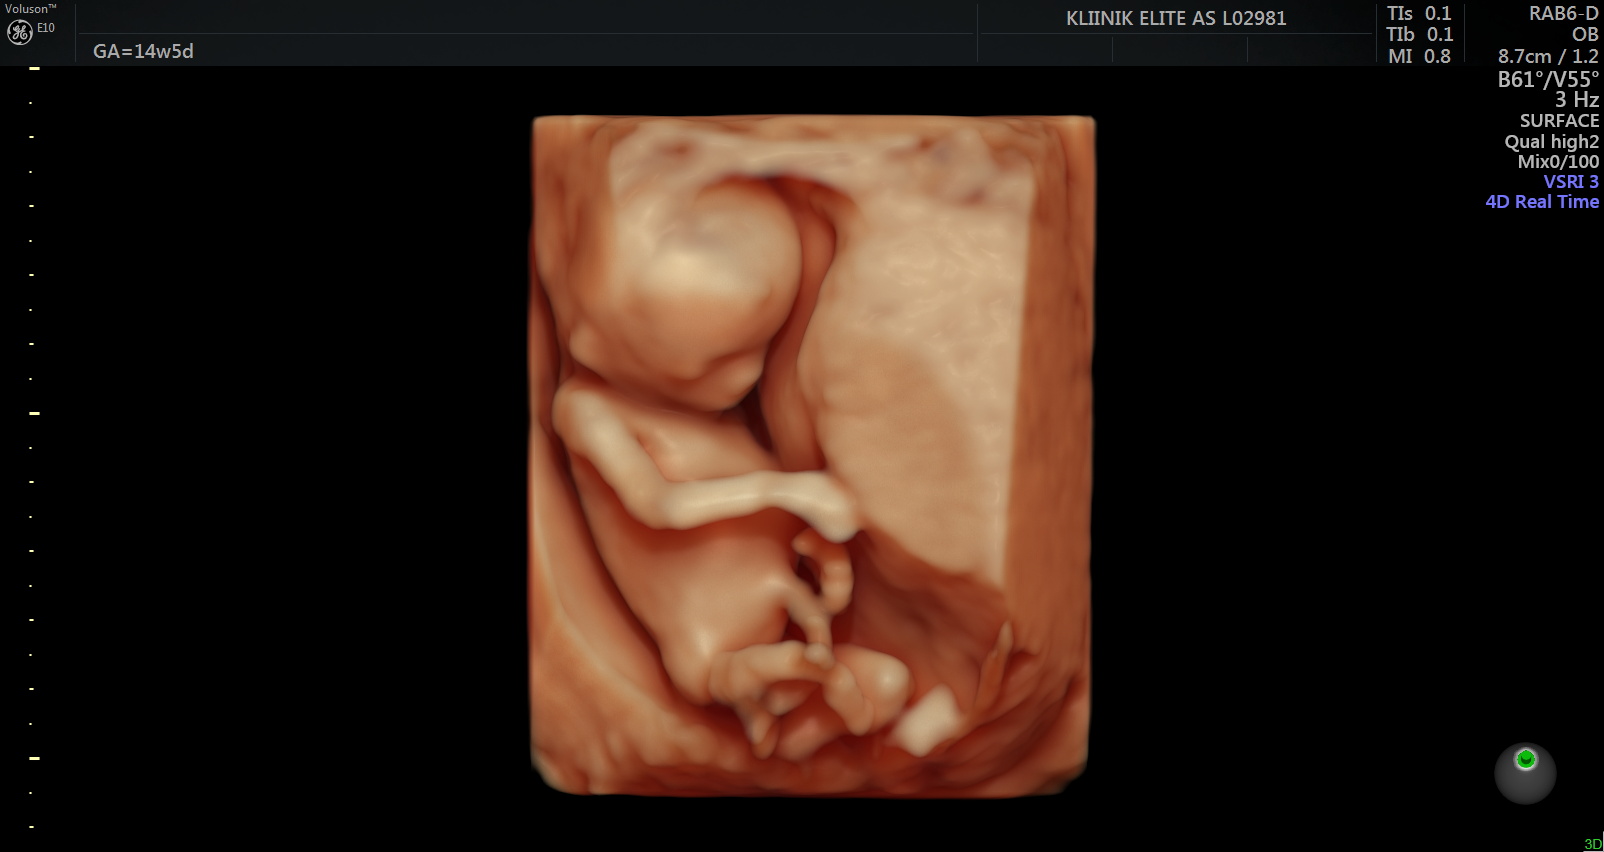

Ultraheliuuringul on loode nähtav. Hakkab moodustuma loote selgroog ning ajul on moodustunud kaks sagarat. Lootel hakkavad arenema käed, jalad ja nägu. 8. nädalal on lootel moodustunud kõik peamised siseorganid. Süda lööb korrapäraselt. Loode on umbes 4 sentimeetrit pikk. Kuni 14.

nädalani mõõdetakse lapse pikkust peast seljani (CLR).

Rasedust saab tuvastada koduse rasedustestiga. Emakaõõnes saab rasedust diagnoosida 6. rasedusnädala alguses (5+). 6.-7. rasedusnädalal saab ultraheliuuringu abil tuvastada loote südametöö ja välistada emakaväline ja peetunud raseduse. Varajane ultraheli (6.-7. nädalal) on oluline ka embrüo väärarengute diagnostikas. Esimesel visiidil teostatakse järgmised analüüsid – vereanalüüs, analüüsid suguteedest, uriiniproov.